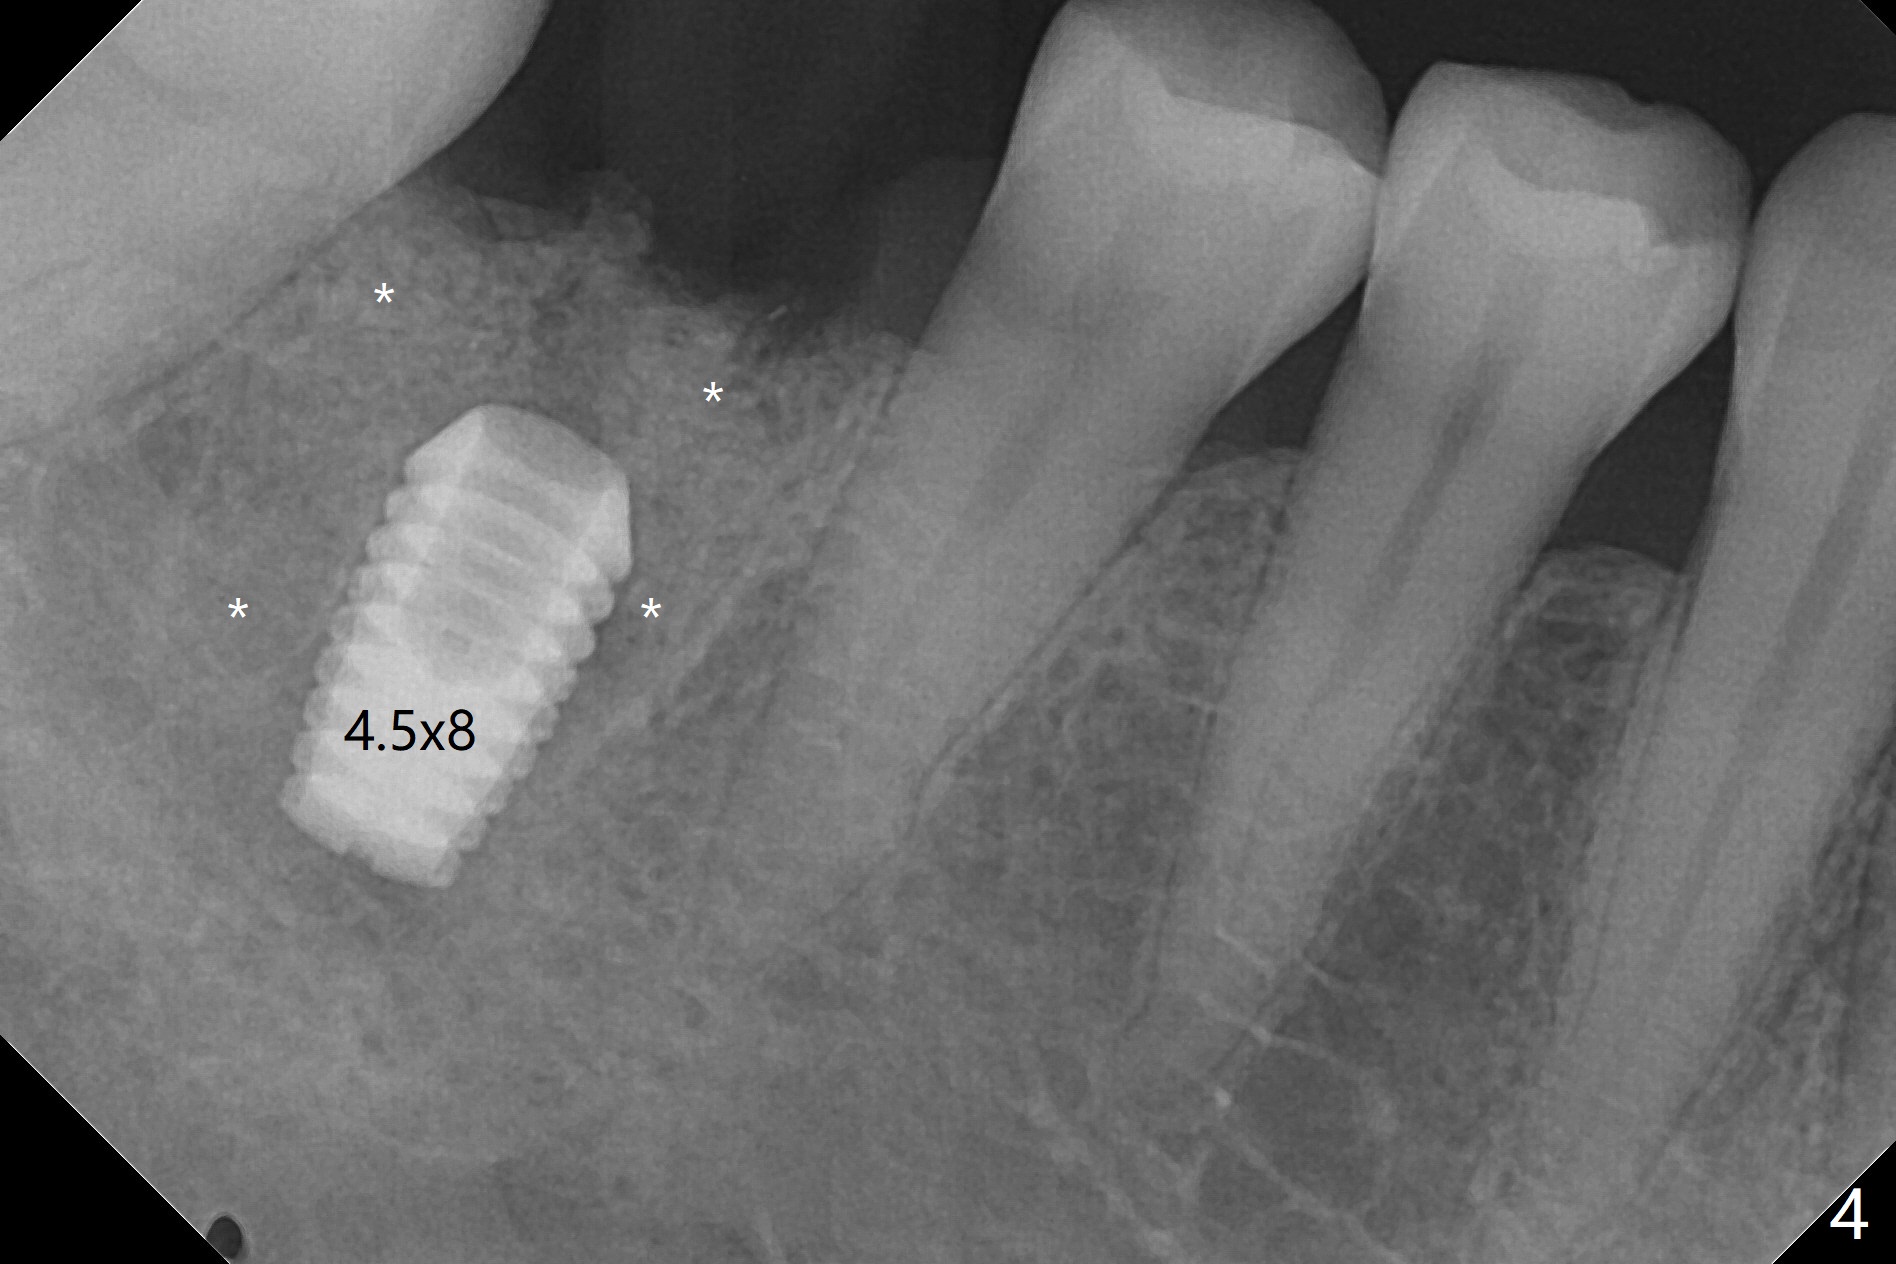

To prevent further postop buccal gingival recession at #30, socket shield is formed with removal of the residual roots (Fig.1,2 *). Osteotomy is initiated in the septum (Fig.2 S, to be flattened with bone trimmer and surgical round bur) and gradually slides slightly into the mesial socket in spite of using surgical guide (Fig.3 *: sleeve). Following 4.5x11.5 mm drill, a 4.5x8 mm Bicon implant is pressed fit; its stability is lightly enhanced with placement of sticky bone in the remaining sockets (Fig.4 *) and around the black plug (Fig.5 P). After removing the coronal portion of the plug to reduce occlusal interference, two pieces of PRF are wrapped around the remaining plug (Fig.6). The main stability of the implant is obtained when setting acrylic (A in Fig.7) is applied into the edentulous space (undercut). After acrylic setting, flowable composite (*) is added distal for further retention. One month postop, the flowable composite is detached. The provisional is sectioned; the black plug is cut. The socket heals with exposure of the mesial socket shield (Fig.8 >). The black healing plug and the mesial socket shield remains exposed 3 months postop (Fig.9). When a 4.5x6.5 mm temporary abutment is placed, the buccal gingiva is blanched and the mesial socket shield is pushed buccal (Fig.10). The implant appears to remain covered by the bone 3 months postop (Fig.11). Cortical bone starts to form crestal 7 months postop (Fig.12 arrowheads, coronavirus). The cortex seems to thicken 8 months postop (Fig.13 *).